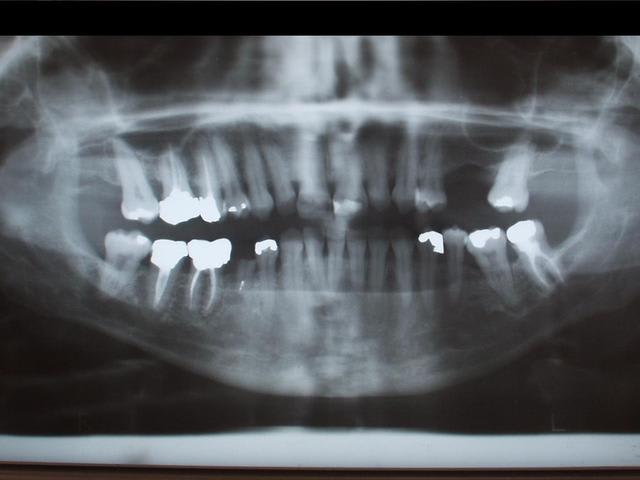

27/06/2006 à 02h04

je confirme,

photo numérique mode makro sans flash avec un bon appui!!

rapide et bonne qualité (elle est en tout cas meilleure que les panos scannés par l'assistante...)

voir ex. ci-joint avec un numérique tout vieux (olympus camedia c220 zoom de seulement 2MPx)